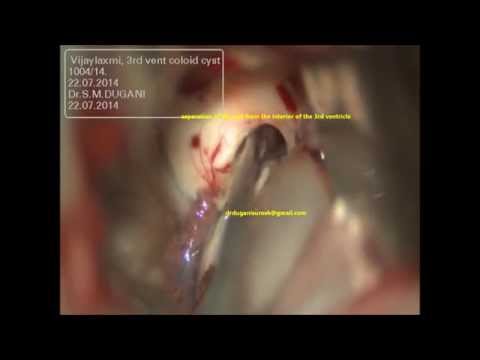

Hellow guys, Welcome to my website, and you are watching COLLOID CYST 3RD VENTRICLE NAVIGATION GUIDED MICROSURGERY -dr suresh dugani/HUBLI/INDIA. and this vIdeo is uploaded by drsuresh dugani NEUROSURGERY EDUCATIVE VIDEOS ATLAS at 2017-07-11T09:30:43-07:00. We are pramote this video only for entertainment and educational perpose only. So, I hop you like our website.